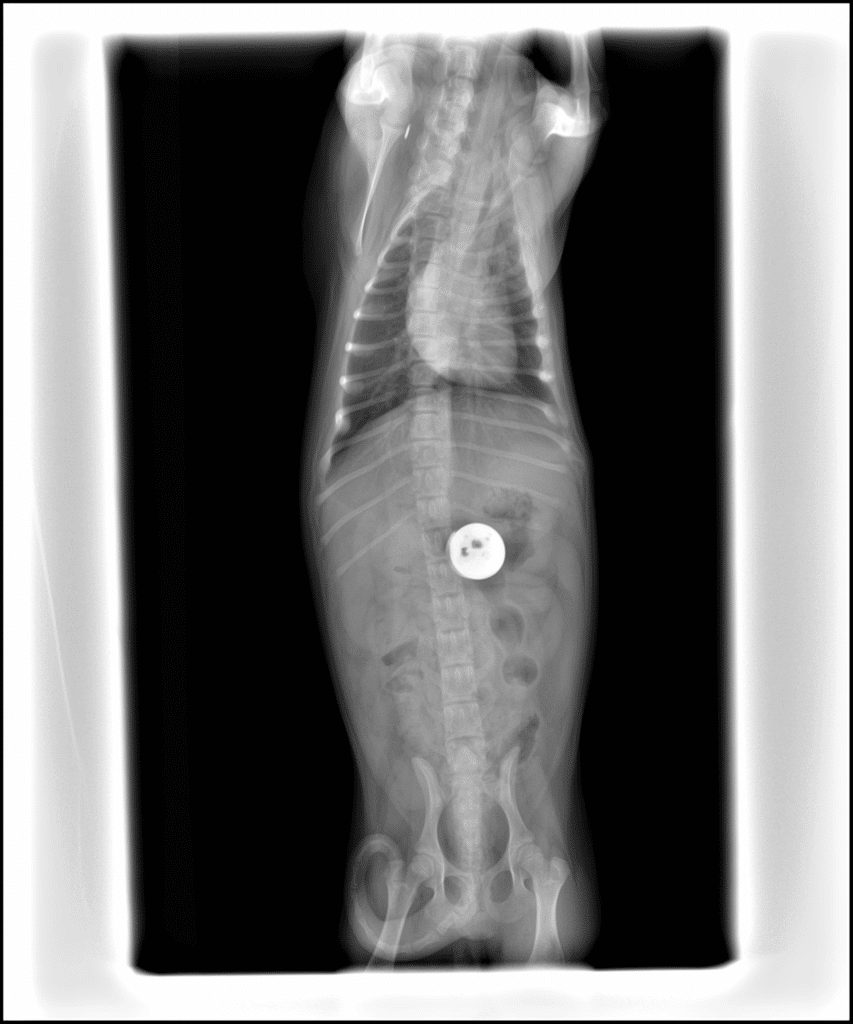

Fast forward to the present and, as a veterinarian at the Schwarzman Animal Medical Center, I routinely encounter patients who eat items with no nutritional value, a condition called “pica.” If you follow us on Facebook and Instagram, you’ve seen the dramatic x-rays of animals that have eaten items like a string of lights, an airtag, rocks, magnets, an ethernet cable and all manner of other non-food items. Today’s blog takes a closer look at pica—what it is, why it happens, and why it matters.

A recent study published in the Journal of the American Veterinary Medical Association reports an association between foreign objects in the stomach and clinical signs of gastrointestinal disease. The authors suggest adult dogs and cats with clinical signs of vomiting, diarrhea, a gastric foreign body and multiple episodes of pica should have biopsies of the stomach and intestine when the foreign body is removed. This can help identify underlying inflammation or disease contributing to the behavior.